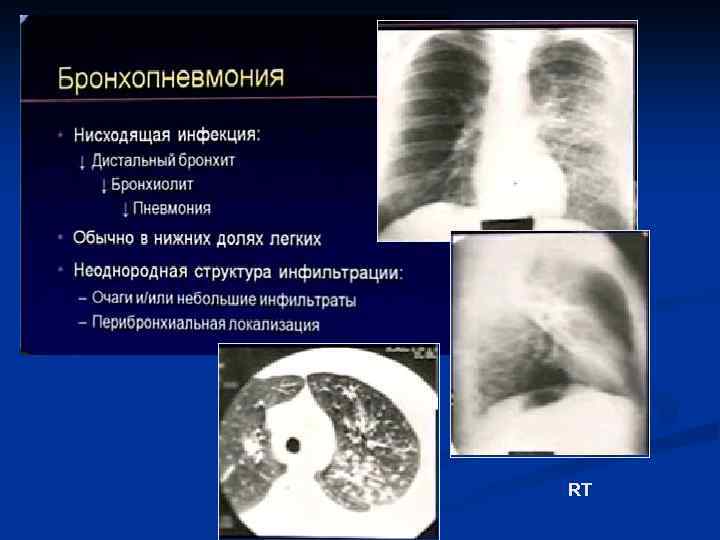

RT

- Центрилобулярные очаги - Симптом «дерева в почках» - Утолщение стенок бронхов

Бронхопневмония Локальный характер изменений (1 -2 сегмента) Перибронхиальные, центрилобулярные очаги или небольшие инфильтраты Субплевральное расположение очагов Контуры очагов достаточно четкие Денситометрическая плотность - +20…+40 HU Просвет бронхов свободен, стенки утолщены, в процесс вовлечены бронхи 5 -7 порядка

Очаги инфильтрации в ндоле сочетаются с усилением легочного рисунка и расширением корня Легочный рисунок усилен, что подчеркивает пестроту картины Корни реактивны Нет четкой границы по ходу междолевой плевры. М. б. очаги в соседних долях